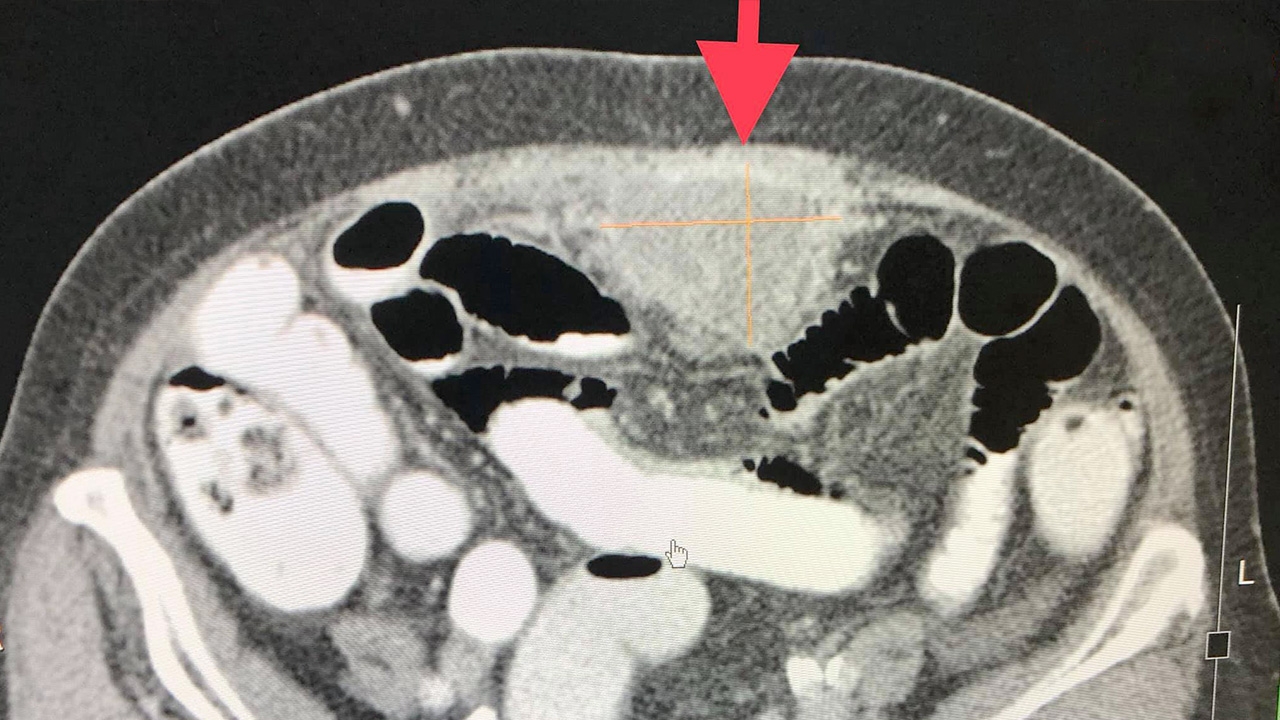

ตรวจร่างกายคลำได้ก้อนแข็งที่หน้าท้องตรงกลางส่วนล่าง ตรวจภายในไม่พบอะไรผิดปกติ ค่า CA125 สูง 879 (ค่าปกติน้อยกว่า 35) ทำคอมพิวเตอร์ช่องท้องพบก้อนขนาด 5.4x3.9x3.4 ซม.ที่ช่องท้องตรงกลางด้านล่าง ไม่พบผิดปกติที่รังไข่ทั้ง 2 ข้าง ได้ใช้เข็มทิ่มที่ก้อน เอาชิ้นเนื้อส่งตรวจ ผลพยาธิวิทยาของชิ้นเนื้อเป็นมะเร็งของเยื่อบุช่องท้อง